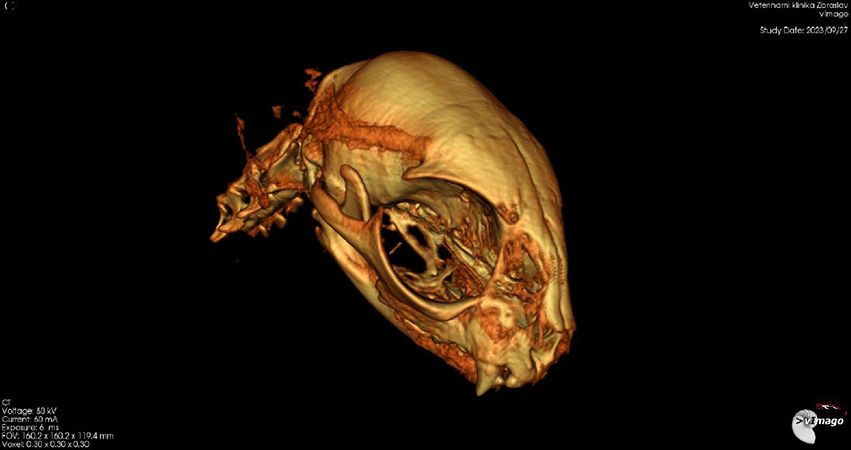

Leo absolvuje nové CT vyšetření. Je zřejmé, že oproti původní diagnóze (špatně zhojené poškození měkkých tkání), je z nových snímků jasně patrné, že Leo má špatně zhojenou zlomeninu spojení spodní čelisti a podočnicového oblouku na levé straně, což je důvod, proč se mu pusinka opět zavřela. Je nutná operace. Po krátké konzultaci v Nuslích Linda domlouvá, aby Lea odoperovali akutně na Zbraslavi. Dostává zprávu, 3D model i CT snímky do mailu.